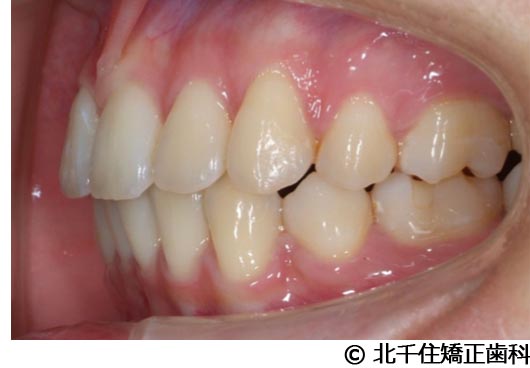

【症例2】上顎前突症

- 治療前

- 治療中

- 治療後

- 治療名

- 上顎前突症

- 費用

- 1,399,000円(税込)

- 期間

- 3年6ヵ月

- 治療回数

- 42回

- 通院頻度

- 1ヵ月ごと

- 年齢・性別

- 19歳10ヵ月・男性(初診時)

治療内容

-

患者様の症状

主訴:出っ歯、口元の突出、横顔をきれいにしたい

治療方法

骨格性の上顎前突、上下顎第一小臼歯4本及び上顎第二大臼歯を抜歯して矯正用アンカースクリューを併用してワイヤー矯正治療(セラミックブラケット)。

治療結果

骨格性上顎前突に対し、抜歯および矯正用アンカースクリューを併用した矯正治療により歯列および咬合関係の調整を行った症例である。治療後は保定装置を使用し、歯列および咬合の安定維持を目的として定期的な経過観察を行っている。

※治療結果は個人差があります。

治療を行う上での注意点(リスク・副作用)

歯磨き不良に伴うカリエスや歯周病、顎関節症、歯根吸収など。